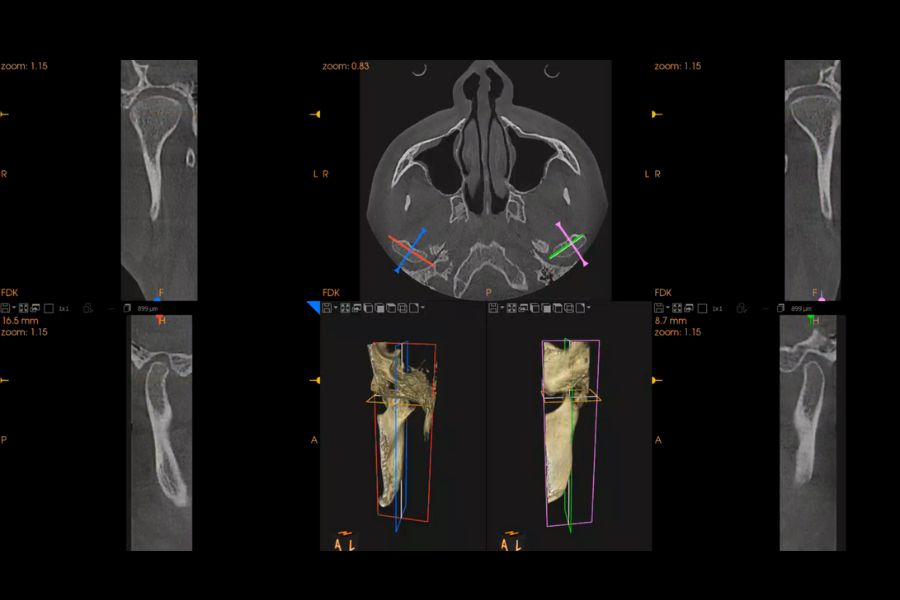

Integración de datos clínicos en 3D

Smile Cloud no trabaja de forma aislada. En este caso, integramos dentro del mismo entorno digital los datos obtenidos mediante escáner intraoral, el estudio CBCT y el análisis del movimiento mandibular.

El CBCT nos permitió analizar en tres dimensiones el hueso, la posición dental y la situación exacta del molar ausente, aportando una base diagnóstica sólida sobre la que construir el tratamiento.

Esta integración permitió ampliar el diseño estético hacia una planificación funcional real, conectando estética, estructura ósea y movimiento.

Análisis funcional 4D con Modjaw

Para estudiar la mordida y el comportamiento de la mandíbula utilizamos Modjaw. Esta tecnología registra los movimientos reales en tiempo real y en cuatro dimensiones.

Gracias a este análisis comprobamos cómo se producía la apertura, la rotación y la posición final de rehabilitación mandibular. Esta información resultó clave para diseñar un tratamiento que no solo se viera bien, sino que funcionara correctamente.

Planificación CAD y guías quirúrgicas

Con todos los datos integrados realizamos un encerado funcional digital y diseñamos guías específicas, como la guía de alargamiento coronario.

Esta fase permitió anticipar cada paso del tratamiento y reducir al mínimo los márgenes de error.